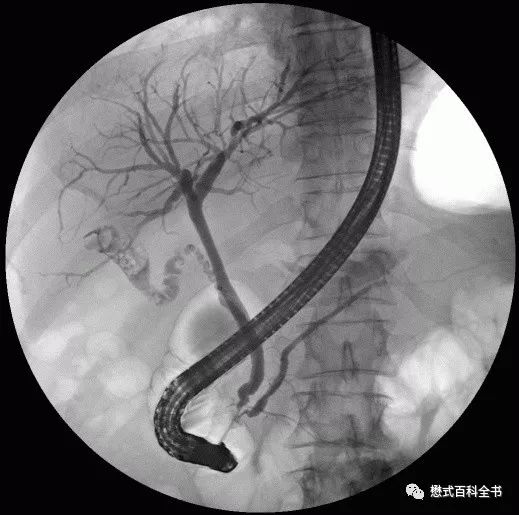

图2、3:ERCP图像

扯回来,胆道系统影像学检查方法很多,除了前面说的MRCP和ERCP,还有X线胆囊造影,CT检查,超声等。不同检查方式有不同的优劣,本期内容我们就不重点讨论这个了。